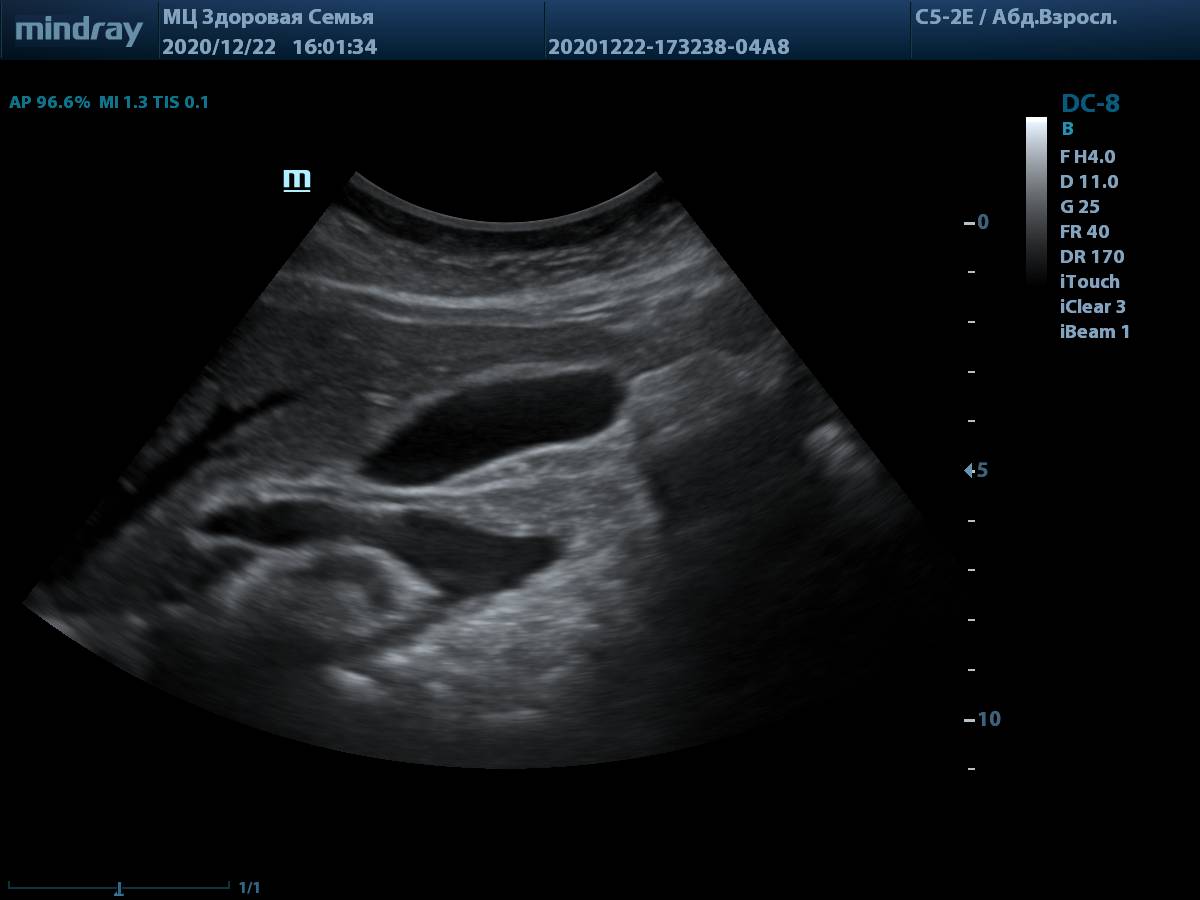

4. Пример визуализации поджелудочной железы у пациента с избытком массы тела, проблем с измерением органа и оценки его структуры нет. В качестве линзы использована левая доля печени.

Визуализации поджелудочной железы